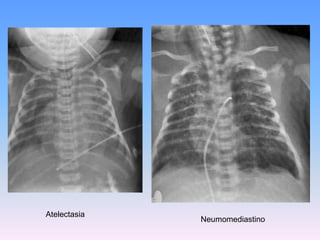

Deberían ser establecidas en RN con LAM si están deprimidos, si necesitan ventilación a presión positiva, o si inicialmente están aparentemente vigorosos, pero que subsecuentemente manifiesten distrés respiratorio dentro de los primeros minutos de vida.Hallazgos RadiográficosHallazgos radiográficos, en infantes con SAM incluyen:Infiltrados difusos.

Consolidación

Atelectasia

Derrame pleural

Espacios aéreos (neumotórax, neumomediastino)

Pulmón húmedo, similar a lo hallazgos vistos en la T.T. RN.

Hipovascularidad

Aparentemente limpio, apariencia virtualmente normal.AtelectasiaNeumomediastino